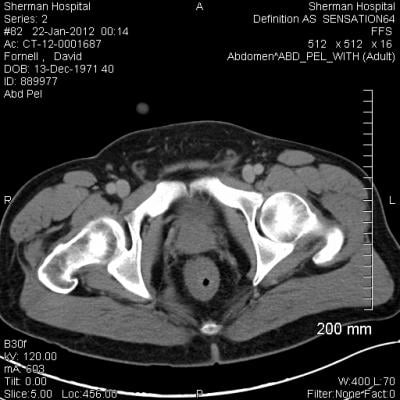

Ten-year findings from the trial indicate that for men with early-stage prostate cancer, there is no difference in mortality rates following active monitoring, surgery or RT. Moreover, cancer-specific deaths at ten years following diagnosis averaged only 1 percent for all men enrolled in the trial.

Growth of the cancer outside of the prostate did vary between monitoring and treatment groups. Rates of both regional spread and distant metastases were significantly higher for men who were monitored rather than treated for their early-stage disease. Progression did not vary, however, between the surgery and RT groups, although patients in the trial reported different side effects with each modality.